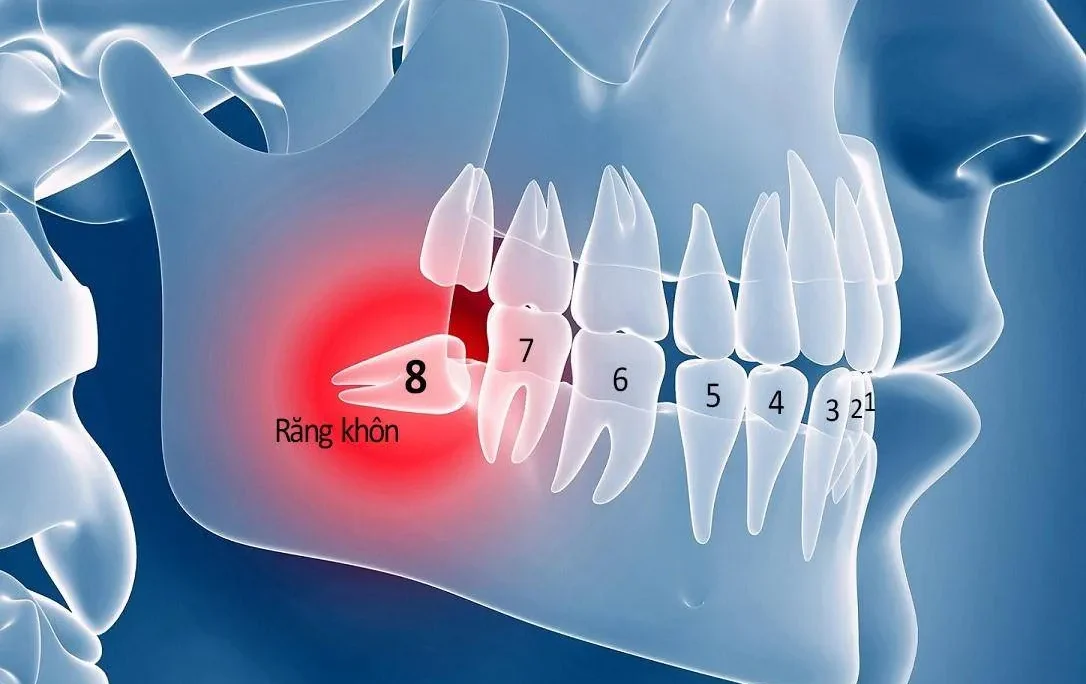

- Răng mọc lệch, mọc ngầm gây ảnh hưởng đến các răng khác.

- Vị trí răng cần nhổ: Các răng hàm lớn và răng khôn nằm gần các dây thần kinh, vì vậy quá trình nhổ có thể gây đau đớn và chảy máu nhiều hơn so với các răng khác. Tuy nhiên, nếu được thực hiện bởi bác sĩ chuyên nghiệp, rủi ro ảnh hưởng đến thần kinh sẽ rất thấp.

- Cam kết an toàn tuyệt đối: Nhổ răng hàm là một ca tiểu phẫu đòi hỏi sự chính xác cao, đặc biệt là với những răng gần các dây thần kinh. Nha khoa Dr.Green đảm bảo thực hiện nhổ răng một cách cẩn thận, không gây tổn thương đến các mô xung quanh và thần kinh, giúp bạn tránh khỏi những biến chứng sau khi điều trị.